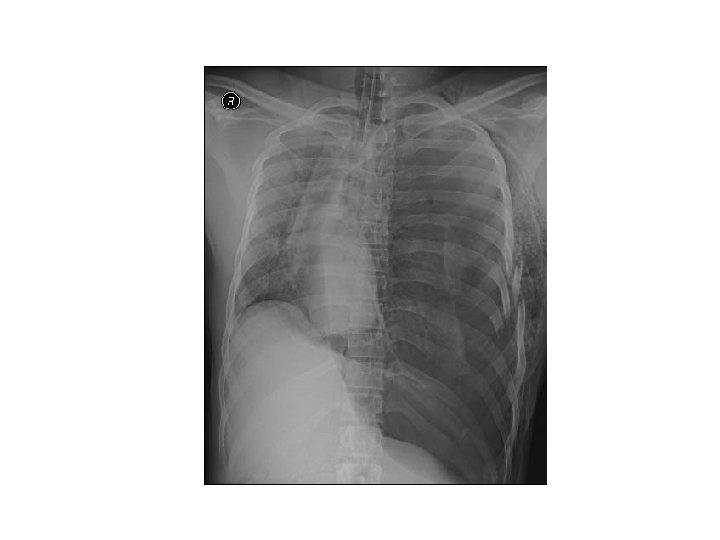

İKİNCİL BAKI • Daha derin fizik muayene • Akciğer filmi, AKG, pulse oksimetre ve EKG’ye bakılır. • Multiple kosta kırığı ve 1. ve/veya 2. kostanın kırılmış olması göğüs duvarı ve derin dokularını şiddetli bir travmaya maruz kaldığını düşündürür.

C. KOSTA, STERNUM VE SKAPULAR KIRIKLAR � Skapula, 1. - 2. kosta veya sternum kırıkları baş, boyun, spinal kord, akciğer ve büyük damar yaralanmaları (mort % 35) � Sternal kırıklarla birlikte pulmoner kontüzyon ve kardiak yaralanma � Genç hastalar � Lokalize ağrı, palpasyonda gerginlik ve krepitasyon kosta yaralanması � Kostakondral ayrılmalar X-ray ile görüntülenemez. � Yeterli ventilasyon için analjezi